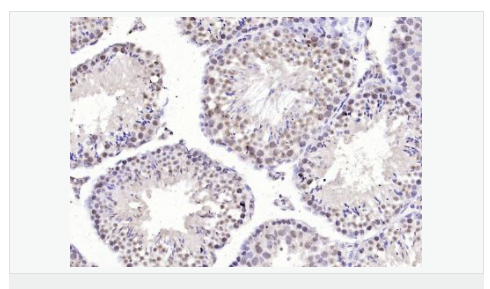

產(chǎn)品應用WB=1:500-2000 ELISA=1:5000-10000 IHC-P=1:100-500 IHC-F=1:100-500 IF=1:100-500 (石蠟切片需做抗原修復)

細胞定位細胞核